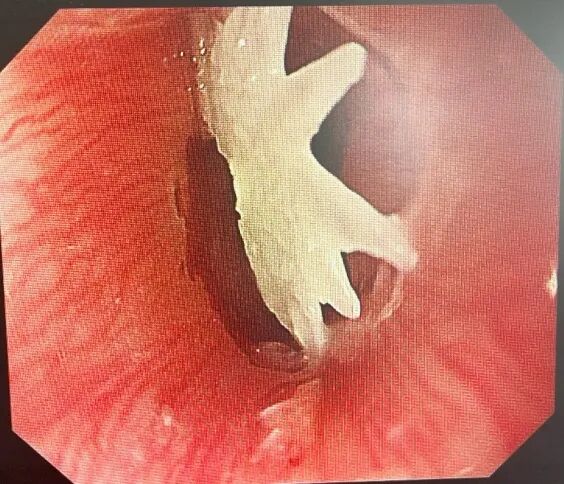

在内镜中心的配合下,消化科团队紧急开展胃镜检查,检查发现一枚不规则鱼骨竟带着多个锋利尖刺,部分已刺入宝宝娇嫩的食管壁,稍有不慎就可能划伤血管、引发穿孔。

03 凭借丰富经验,完整取出“肉中刺”

最终,凭借丰富的内镜经验,手术团队小心翼翼操作,终于将这颗 “肉中刺”完整取出,家长看着带血的鱼骨,后怕不已。